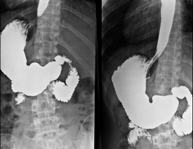

Prova diagnòstica que consisteix en obtenir imatges radiològiques en moviment de l'esòfag mitjançant l'ús de raigs X (fluorosòpia) i d'un contrast opac baritat que s'administra per via oral.

Tècnica que usa els raigs X a través de la qual s'obtenen imatges de la columna lumbar per al seu estudi. - TEGD (trànsit esòfag-gastro-duodenal)

Prova diagnòstica que consisteix en obtenir imatges radiològiques en moviment de l'esòfag, estómac i duodè mitjançant l'ús de raigs X (fluoroscòpia) i d'un contrast opac baritat que s'administra per via oral. - Trànsit intestinal

Prova diagnòstica que consisteix en obtenir imatges radiològiques en moviment de l'esòfag, estómac, duodè i intestí prim mitjançant l'ús de raigs X (fluoroscòpia) i d'un contrast opac baritat que s'administra per via oral. - Ènema opac doble contrast

Prova diagnòstica que consisteix en obtenir imatges radiològiques de l'intestí gros (còlon i recte) mitjançant l'ús de raigs X. S'utilitza un contrast opac que s'administra a través del recte en forma d'ènema i també s'introdueix aire per expandir el còlon.